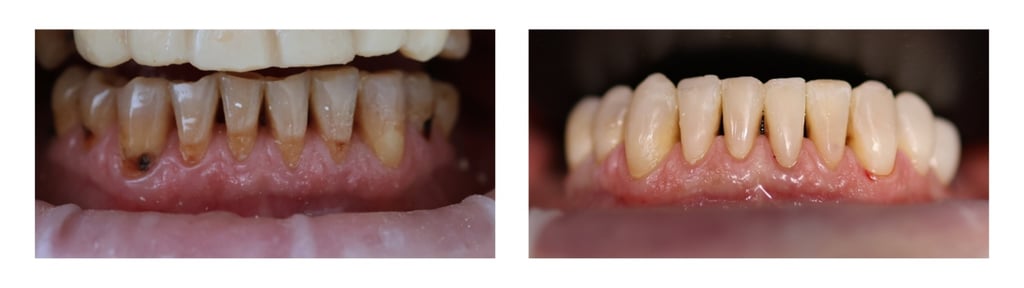

MŪSŲ DARBAI

Apatinių dantų gydymas ir plombavimas kompozitinėmis restauracijomis.